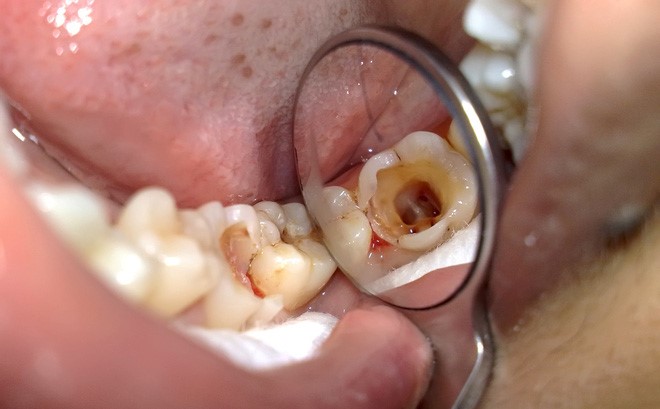

(Trám răng sẽ không bền nếu như bề mặt răng đã bị phá hủy nghiêm trọng)(**)